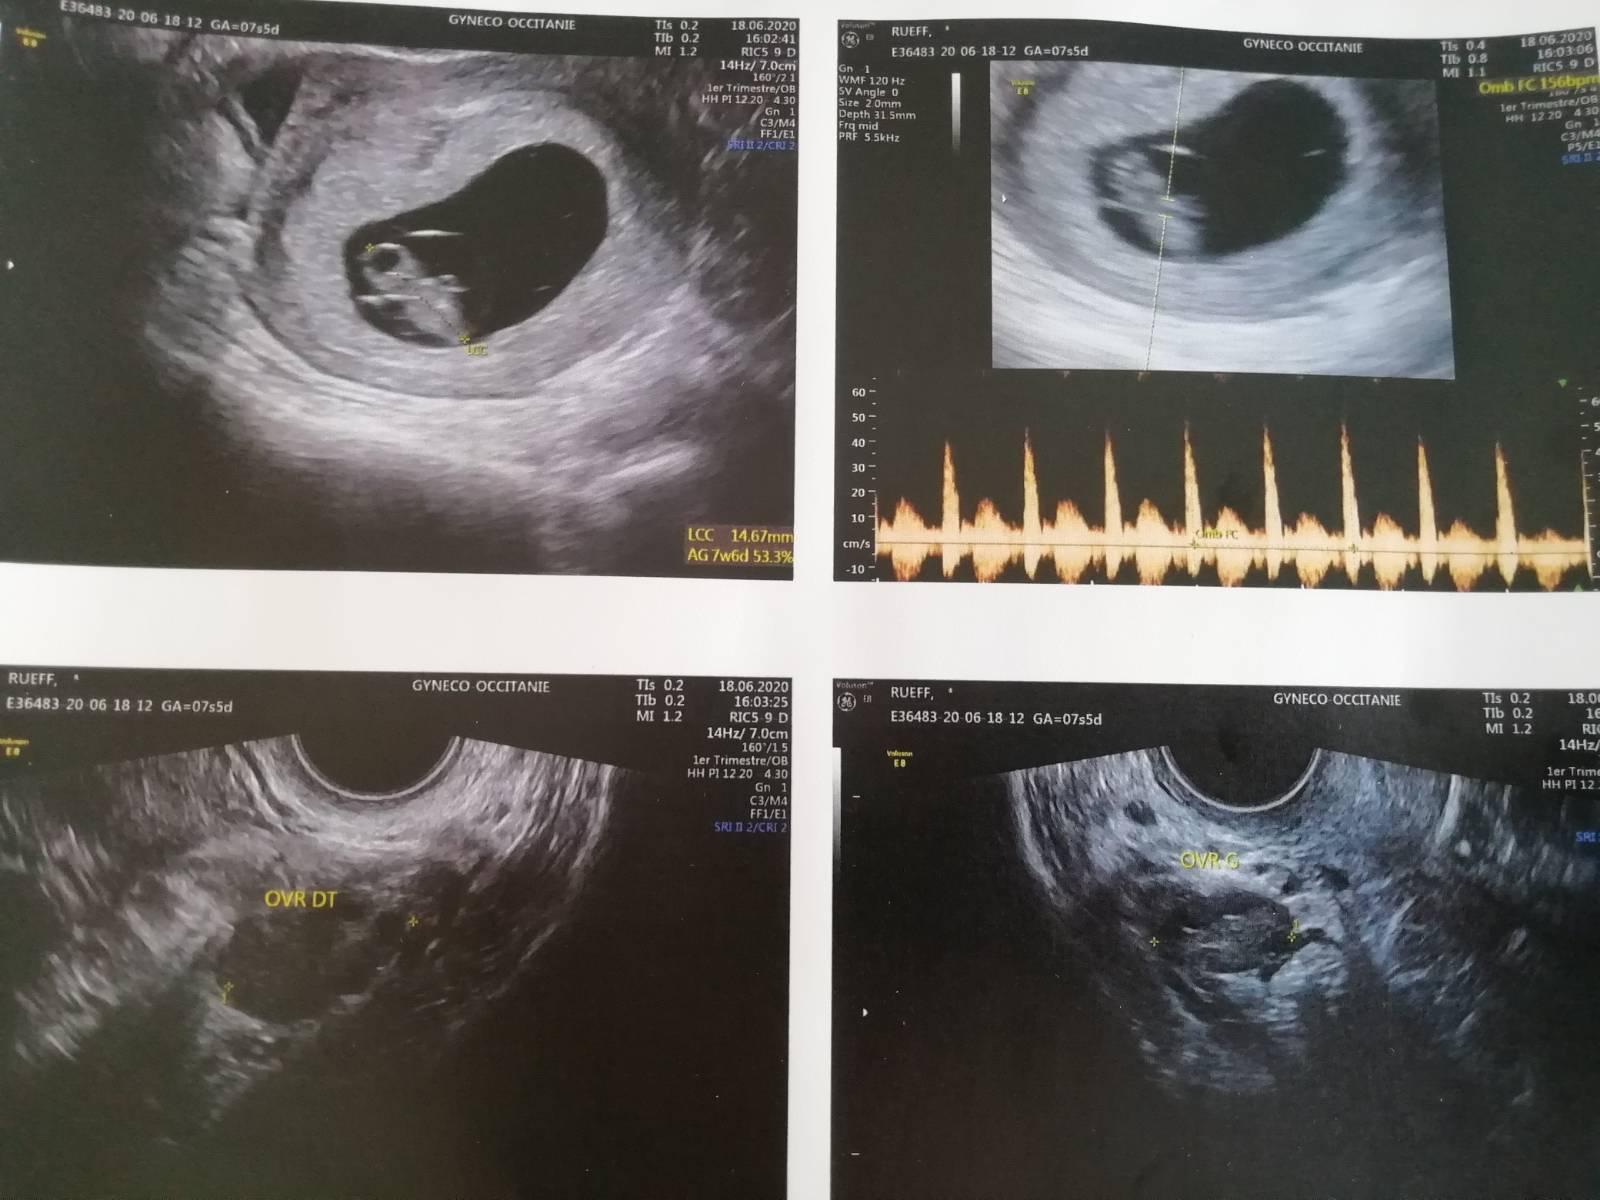

สวัสดีค่ะแม่ๆทุกคน วันนี้มาขอแชร์ประสบการณ์ท้องแรกที่รอมาห้าปี แต่สุดท้ายน้องก็อยู่กับเราแค่ 14 ชม. น้องก็จากเราไป 😭😭😭 ขอเล่าตั้งแต่แรกๆเลยละกันนะคะ เราอยู่กินกับสามีที่ฝรั่งเศสมาห้าปี เราอยากมีลูกมาก ช่วงกลางปี2019 เราและสามีได้เข้าไปปรึกษาแพทย์เฉพาะทางดูว่าทำไมถึงไม่มีน้องสักที 😢เริ่มที่ตัวสามีหมอก็ให้ตรวจสเปิร์ม ผลออกมาก็ปรกติดี เราก็เริ่มคิดละว่าต้องมีอะไรผิดปกติในตัวเราแน่เลย(เรากับสามีเป็นคนไม่ดื่ม ไม่เที่ยว ไม่สูบบุหรี่) หมอก็นัดตรวจภายใน อัลตราซาวด์ ทั้งมดลูก ปีกมดลูก รังไข่ และให้ใบนัดไปตรวจเลือด ให้ยาบำรุงมาทาน พอถึงวันนัด เรากลัวมาก กลัวว่าตัวเองจะไม่สามารถมีลูกได้ คิดไปต่างๆนาๆ หมอ บอกว่าจากภาพอัลตร้าซาวด์คุณมีปัญหาที่ปีกมดลูก หมอก็ให้เราไปตรวจ(écophotographie)ดูให้แน่ชัดในวันเดียวกันโดยการฉีดอะไรบางอย่างเข้าไปในมดลูกเราไม่แน่ใจว่าที่ไทยเขาเรียกว่าอะไร บอกเลยว่าเจ็บมาก ปากเป็ดคารู สายยางที่ฉีดยาเข้าช่องคลอดก็คารูอยู่ แถมให้เราตะแคงซ้าย ตะแคงขวา ห้องตรวจก็เย็นมาก หนาวสุดๆ แต่ก็ต้องทน สุดท้ายผลคือ ปีกมดลูกตันค่ะ ด้านซ้ายและด้านขวาก็กำลังจะตันอีกข้าง หมอบอกยังมีหวังค่ะข้างเดียวก็มีได้ แต่ถ้าอยากมีเลยก็ต้องนัดหมอทำกิฟต์ แต่บอกเลยว่าคิวยาวเป็นปีค่ะ เราสองคนเลยตัดสินใจยังไม่ทำ รอไปก่อนเพราะตัวเราเองก็พึ่งได้งานทำ เป็นโรงงานผลิตชิ้นส่วนเครื่ิองบิน (ที่สำคัญคือเขามีข้อห้ามคนท้องทำงานที่โรงงานดัดขาด) เพราะทั้งยกของหนักและมีสารเคมี จากนั้นเราก็ตั้งใจทำงาน ทั้งงานที่โรงงาน (จันทร์-ศุกร์ ) มีทำอาหารไทยส่งตามบ้าน และรับนวดตามบ้านด้วย (เสาร์-อาทิตย์) ยอมรับว่าค่อนข้างทารุณร่างกายตัวเองมาก 😬😬 แต่ก็สู้ค่ะ พอได้มาอีกสักพัก ช่วงต้นปี 2020 โควิด 19 เริ่มระบาด โรงงานก็เริ่ม ให้พน. หยุด งานนวดก็ไม่มี ลูกค้ากับข้าวก็หายหมด แต่ในความเลวร้ายก็ซ่อนความหวังอยู่ ประจำเดือนเราไม่มาขาดไปหนึ่งอาทิตย์ เราก็ไม่ได้เอะใจอะไรเพราะจะเป็นแบบนี้ประจำบางทีสองอาทิตย์ด้วยซ้ำ แต่ก็แอบหวังลึกๆว่าตัวเองจะท้องรึปล่าว😁😁พอเช้าวันที่3-06-20 เราก็ได้หยิบที่ตรวจครรภ์(หมดอายุแล้วสามปี)มาตรวจดู (ตอนนั้นสามีไม่อยู่ นางออกไปเดินออกกำลังกายกับเพื่อนบ้าน) ผลคือขึ้นสองขีดจ้าาาา วินาทีนั้นคือดีใจมาก แต่ก็ยังไม่แน่ใจ เลยบอกให้สามีแวะซื้อที่ตรวจมาตรวจซ้ำอีกที ผลคือขึ้นสองขีดเหมือนเดิม เรากับสามีดีใจจนทำอะไรไม่ถูก 🥳🥳 จากนั้นเราก็ให้สามีนัดหมอฝากครรภ์ นัดตรวจเลือด และอัลตร้าซาวด์ บอกเลยตื่นเต้นมากที่ได้เห็นเจ้าตัวน้อยๆ 💞💞💞